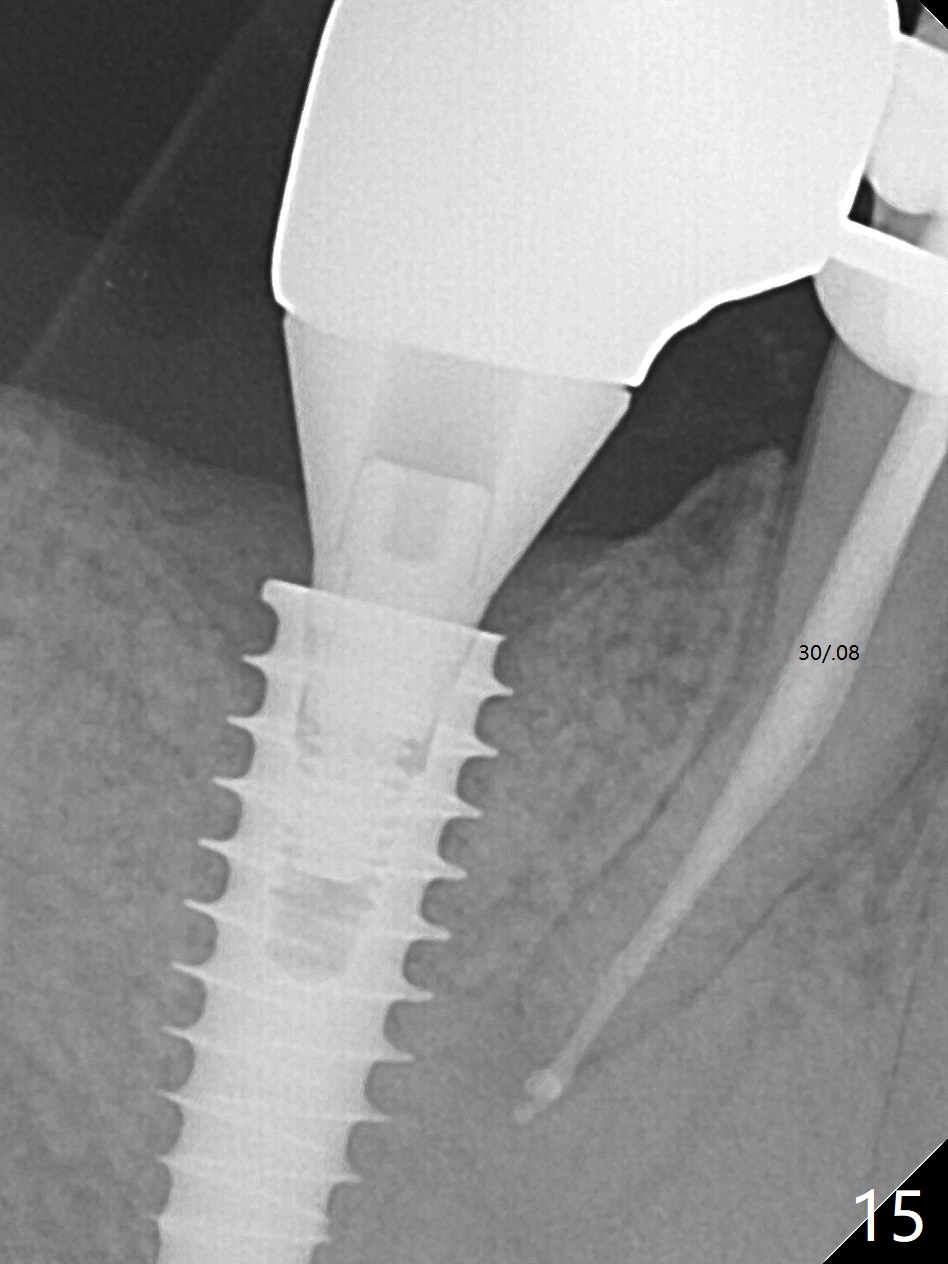

Bone graft seems to sink down and becomes denser 3 months postop (Fig.6 arrow). The bone continues being denser 5 months postop (Fig.7). There is periapical radiolucency of the tooth #29 (^). RCT is done (Fig.8). The pain persists 2 weeks postop (Fig.9,10). There is no missing canal (Fig.9). The apex is close to the implant (Fig.9 *). Apicoectomy will be performed if needed. It appears that the implant is also placed buccal (Fig.10 <) and/or the implant too large for the site. Therefore there should be a 2-3 mm buccal gap before and after implant placement. Separation and reflection of the buccal flap allows better visibility. The pain persists 1 month post RCT and 6 months post implant placement. RCT retreatment is initiated (Fig.11,12) with placement of Calcium Hydroxide paste after redebridement with 30/.04 rotary file at 23.5 mm (.5 mm longer than the earlier RCT, Fig.13). RCT retreatment finishes with apparent transportation and extrusion in 4 weeks (Fig.14,15), followed by apicoetomy (Fig.16,17) (20 days later)). Discomfort remains 2.5 months postop (Fig.18). Keep watching.